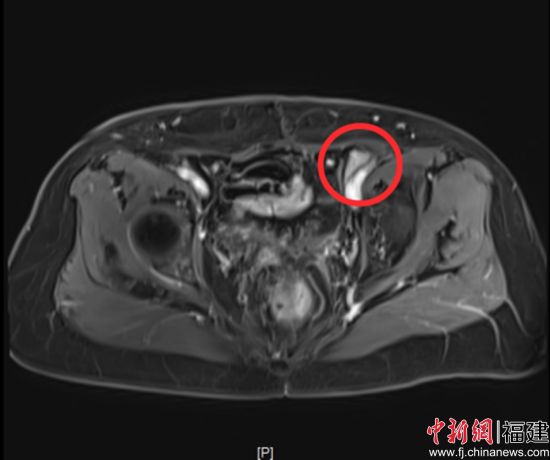

治疗过程顺利,相关指标逐步好转。用药2周期后,疗效评价即达到部分缓解(PR);用药6周期后,疗效评估进一步提升,达到完全缓解(CR)。更令人欣慰的是,整个治疗过程中患者耐受性良好,未出现严重血液学毒性及胃肠道反应,生活质量得到有效保障。目前,患者仍在维持用药中,持续受益于该治疗方案。